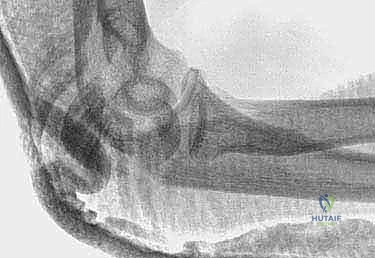

Image

TECH FIG 1 • A. A lateral radiograph with the arm in plaster shows a transverse, noncomminuted fracture of the olecranon. B. An open reduction is held with a fracture reduction forceps.